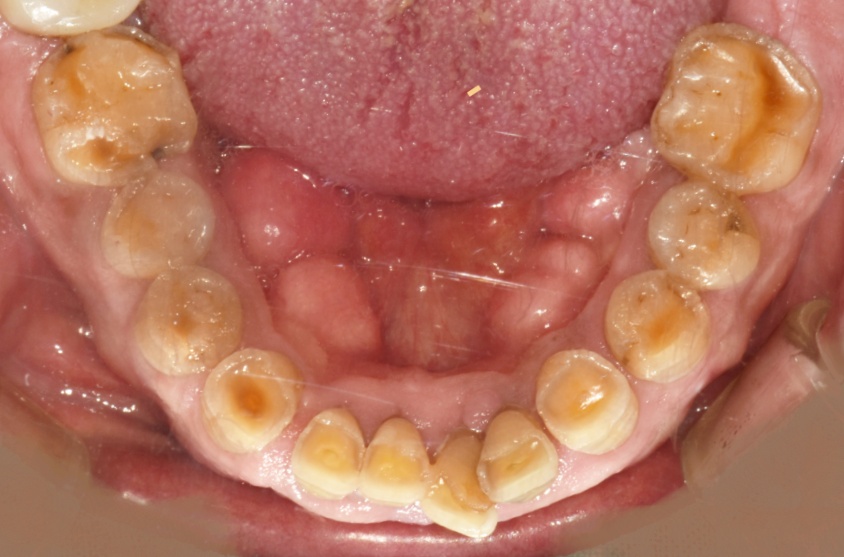

치아가 많이 갈려있다면, 한번 의심해 보세요

심하면 이렇게까지 진행되기도 합니다. 이러면 치료가 상당히 힘들어집니다…​